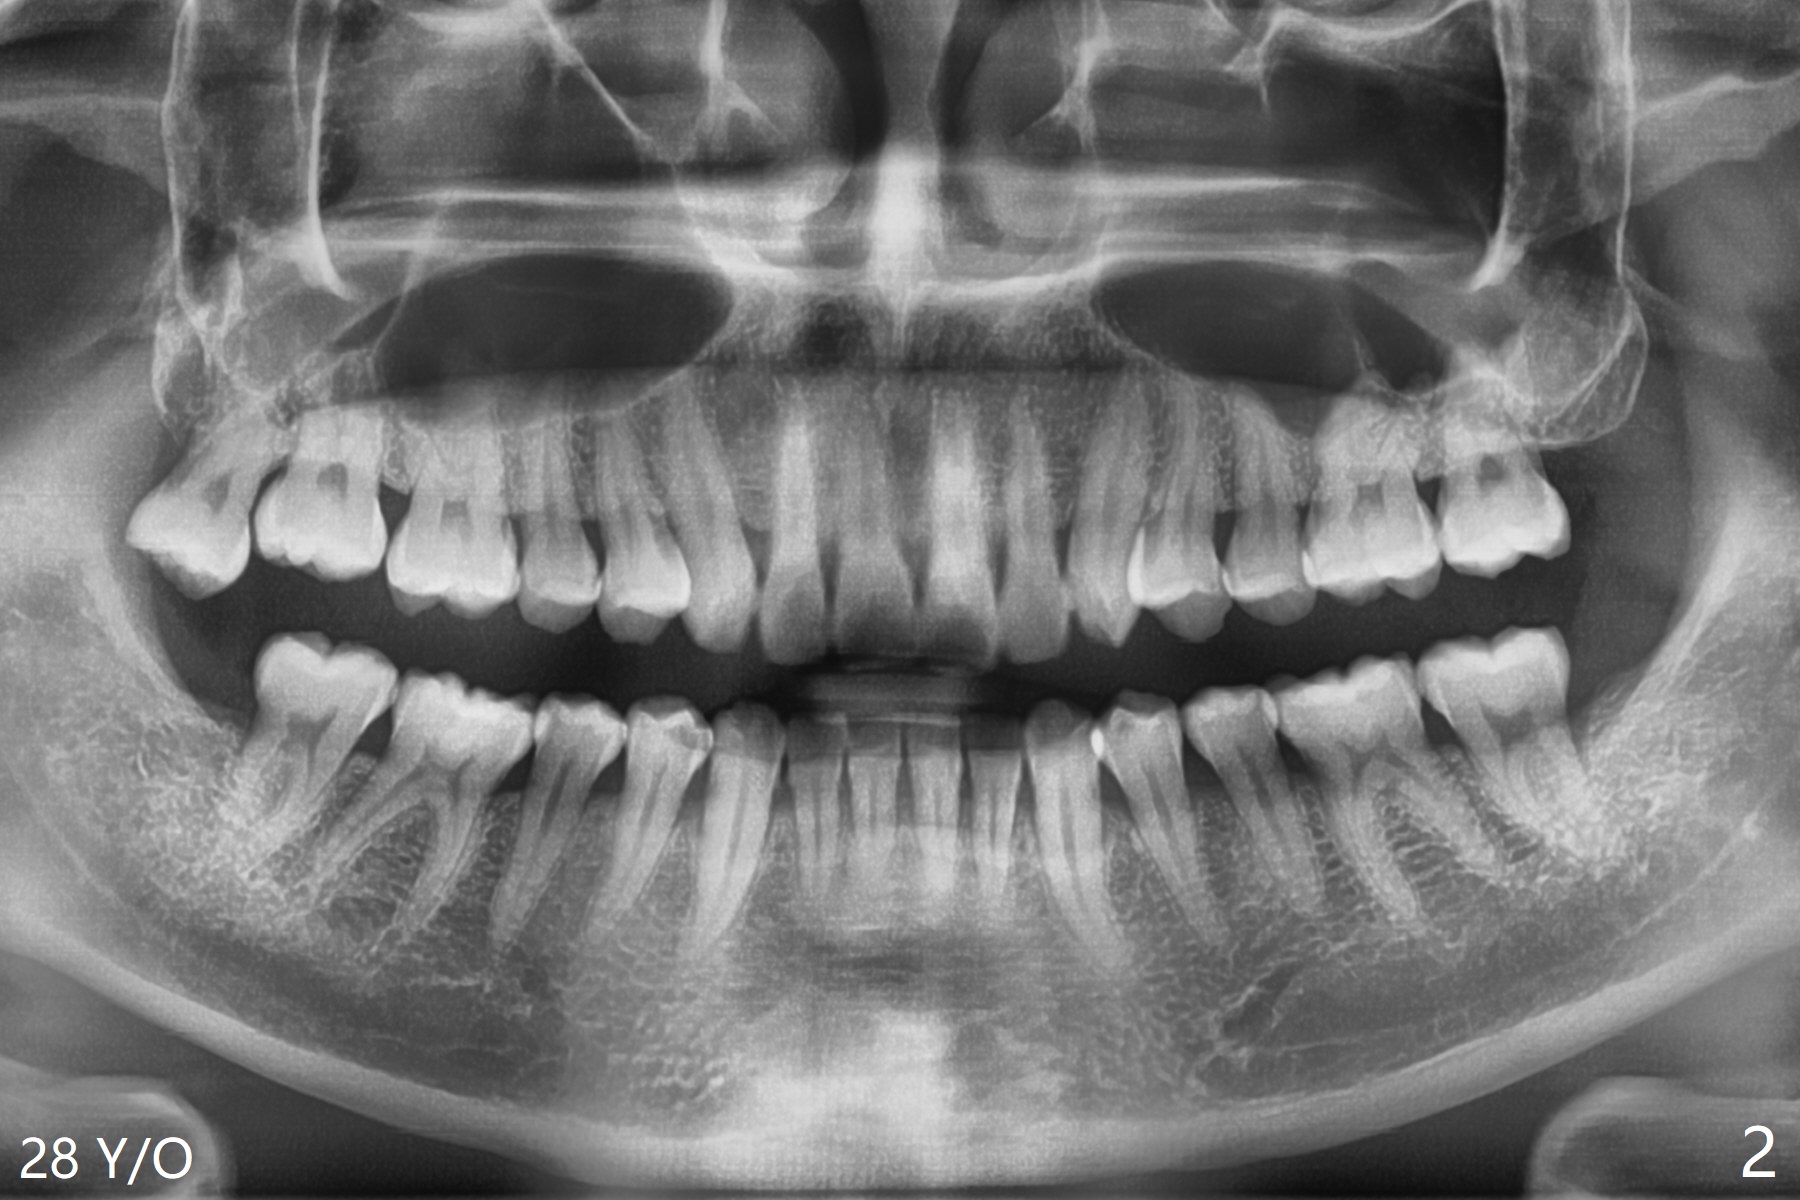

A 24-year-old man presents to clinic for #16, 17 and 32 extraction (Fig.1). Osteogen plug is placed in the last two sockets. All of the 3 sockets heal 4 years later (Fig.2). The tooth #1 is extracted.